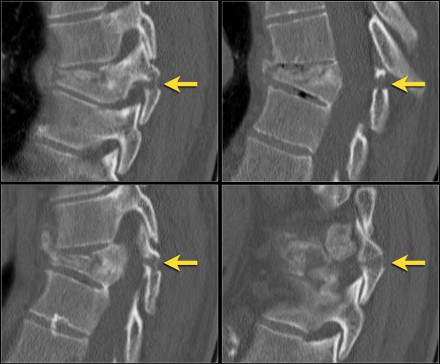

The findings are:

- The main feature is posterior distraction with horizontal fractures of posterior elements (red arrow)

- Avulsion of a spinous process (yellow arrow)

- Widening of facet joint (green arrow)

- Burst-type fracture

In this case some would call this a burst fracture with PLC-injury i.e. 2+3 points.

However the distraction is the most important finding, i.e. distraction and PLC injury, i.e. 4+3 points.